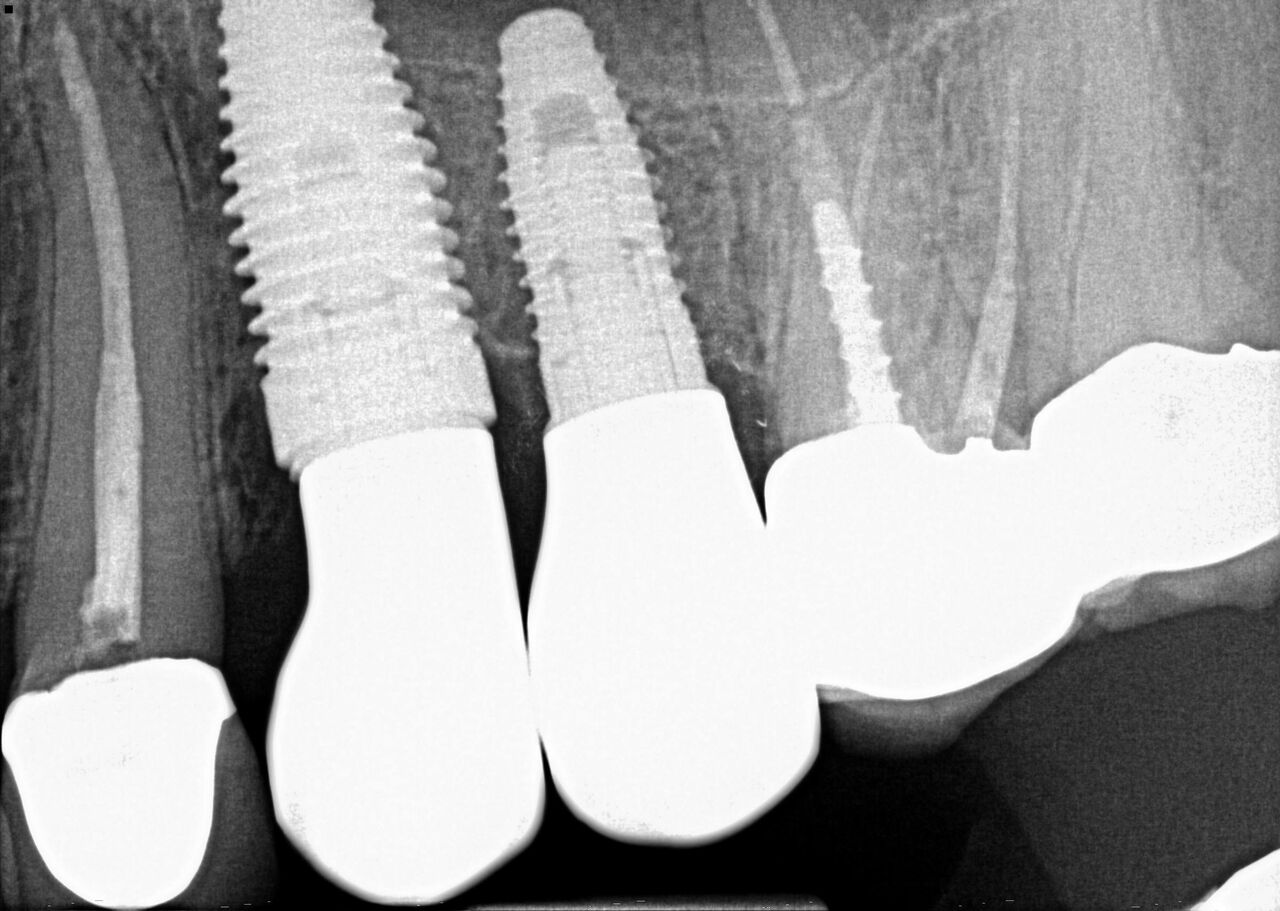

(1.) Case 1 initial radiograph of No. 19.

Figure 1

(4.) Radiograph showing immediate implant of No. 19 with immediate restoration day of surgery.

Figure 4

(6.) 1-year postoperative radiograph of No. 19 IIIPR.

Figure 6

A 63-year-old woman presented with severe pain on biting of tooth No. 19 (Figure 1). Clinically there was pain on percussion and significant periodontal probing along the mesial root. The patient was anesthetized with infiltration anesthesia and the crown was horizontally sectioned from the lingual of the tooth. The remaining tooth was sectioned so the roots could be extracted individually. The socket was fully debrided and an implant was placed (Figure 2), which was prosthetically correct and stabilized in excess of 45 Ncm. The bone was milled to allow for unimpeded placement of a temporization abutment. The initial crown was revised to be the temporary crown in infraocclusion. Cement was extruded extraorally (Figure 3) prior to seating of the temporary restoration. The socket was sealed with the temporary crown and there were no sutures or bone graft (Figure 4 and Figure 5).

The patient was instructed in postoperative care specific to an immediately provisionally restored implant and an antibiotic and analgesic was prescribed. At 4 months, integration was confirmed. The patient was impressed for a final restoration that was cemented within 2 weeks. The final radiograph (Figure 6) and clinical photo (Figure 7) presents a 1-year postoperative demonstrating good esthetics, full bone regeneration, and a steady state of bone to the implant under loading.